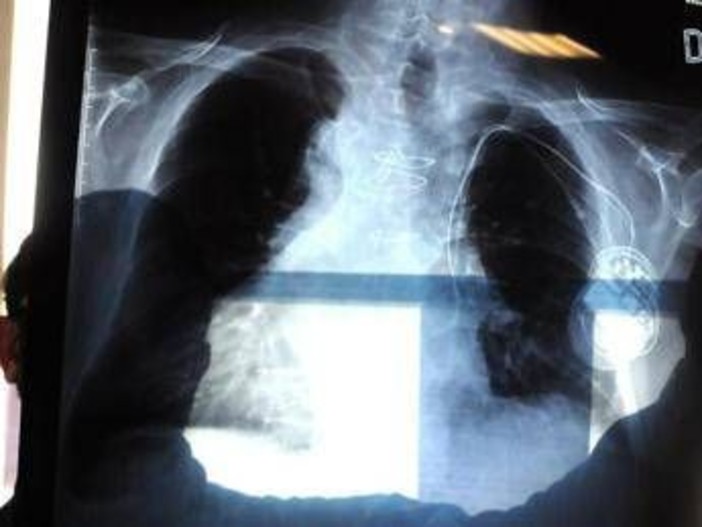

La polmonite, prosegue il presidente di Aipo, è un'infezione che "può essere localizzata in un punto particolare del polmone. L'ente patogeno più frequente in questo caso è lo pneumococco, contro il quale esiste appunto una vaccinazione. Esistono poi le polmoniti interstiziali che colpiscono il tessuto connettivo del polmone, l'area dove avviene lo scambio, per questo l'infezione può essere molto diffusa e anche bilaterale. E' dovuta prevalentemente a virus, il Covid tra questi, come abbiamo visto durante la pandemia, e ad alcuni batteri. Altro caso abbastanza emblematico è la legionella, oppure i cosiddetti agenti intracellulari, micoplasma e clamidia". L'intestizio, precisa Micheletto, "è il tessuto di sostegno del polmone, dove avviene il passaggio dell'ossigeno e dell'anidride carbonica nel senso contrario, tra gli alveoli e i capillari. Quando questo interstizio viene colpito, lo scambio viene notevolmente ridotto. Ma se il paziente ha la bronchite cronica o è un fumatore, questi spazi sono già compromessi. E quindi può dare casi gravi".